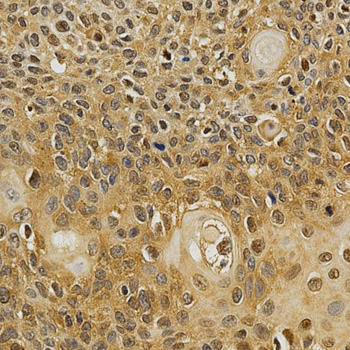

Immunohistochemistry of paraffin-embedded human esophageal cancer using NFATC1 antibody at dilution of 1:200 (x400 lens).